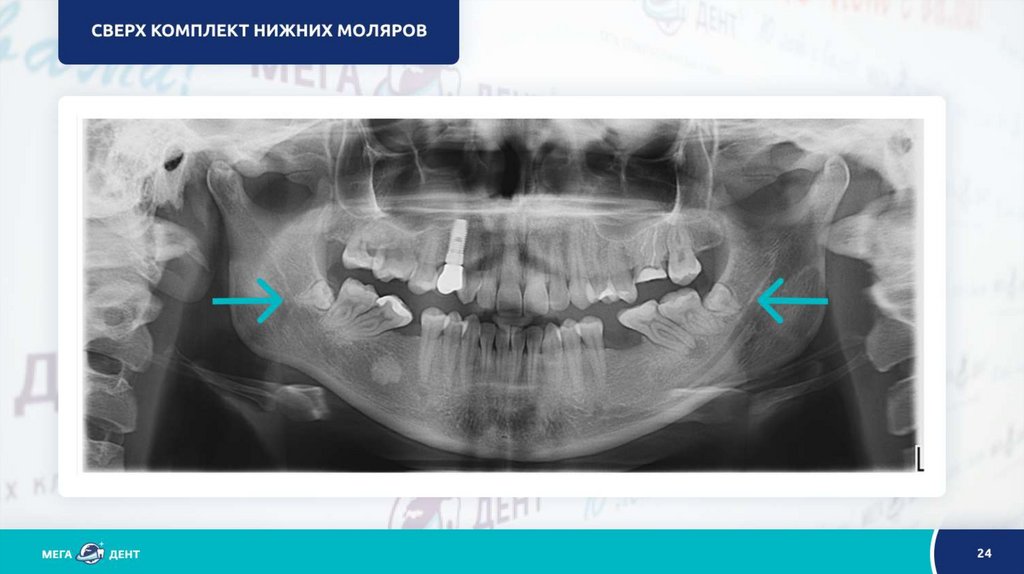

Рентгендиагностика в стоматологии